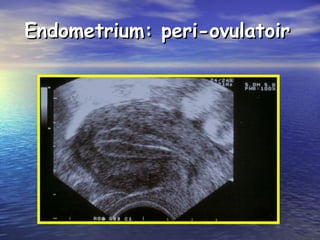

Endometrium: peri-ovulatoirEndometrium: peri-ovulatoir